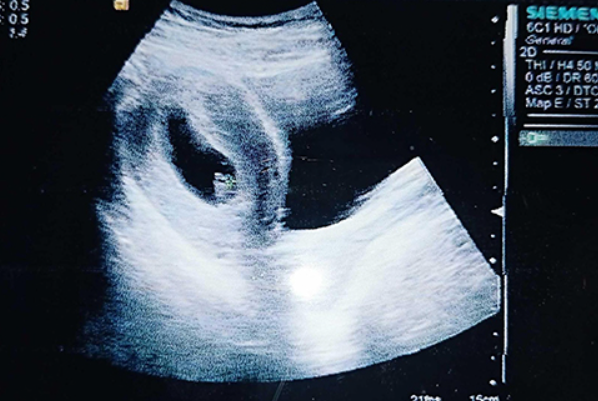

孕囊形状看性别超准方法分享,已生男孩的孕囊图片参考

对于准妈妈来说,在确定怀孕以后,很想知道胎儿性别是男孩还是女孩,会通过生男生女的特征判断胎儿性别,最近在网络上有宝妈分享已生男孩孕囊图片,据说孕囊形状呈长条形或茄子形,可能生男孩,如果孕囊形状呈圆形或椭圆形,那么生女孩的几率较大,很多准妈妈都想试一试,但是仍然有孕妇不知道哪种孕囊属于茄子型,下面详细为大家介绍生儿子孕囊形状图,一起来看看吧。已生男孩阴超孕囊参考图片B超是孕初期重要检查项目,在怀孕1